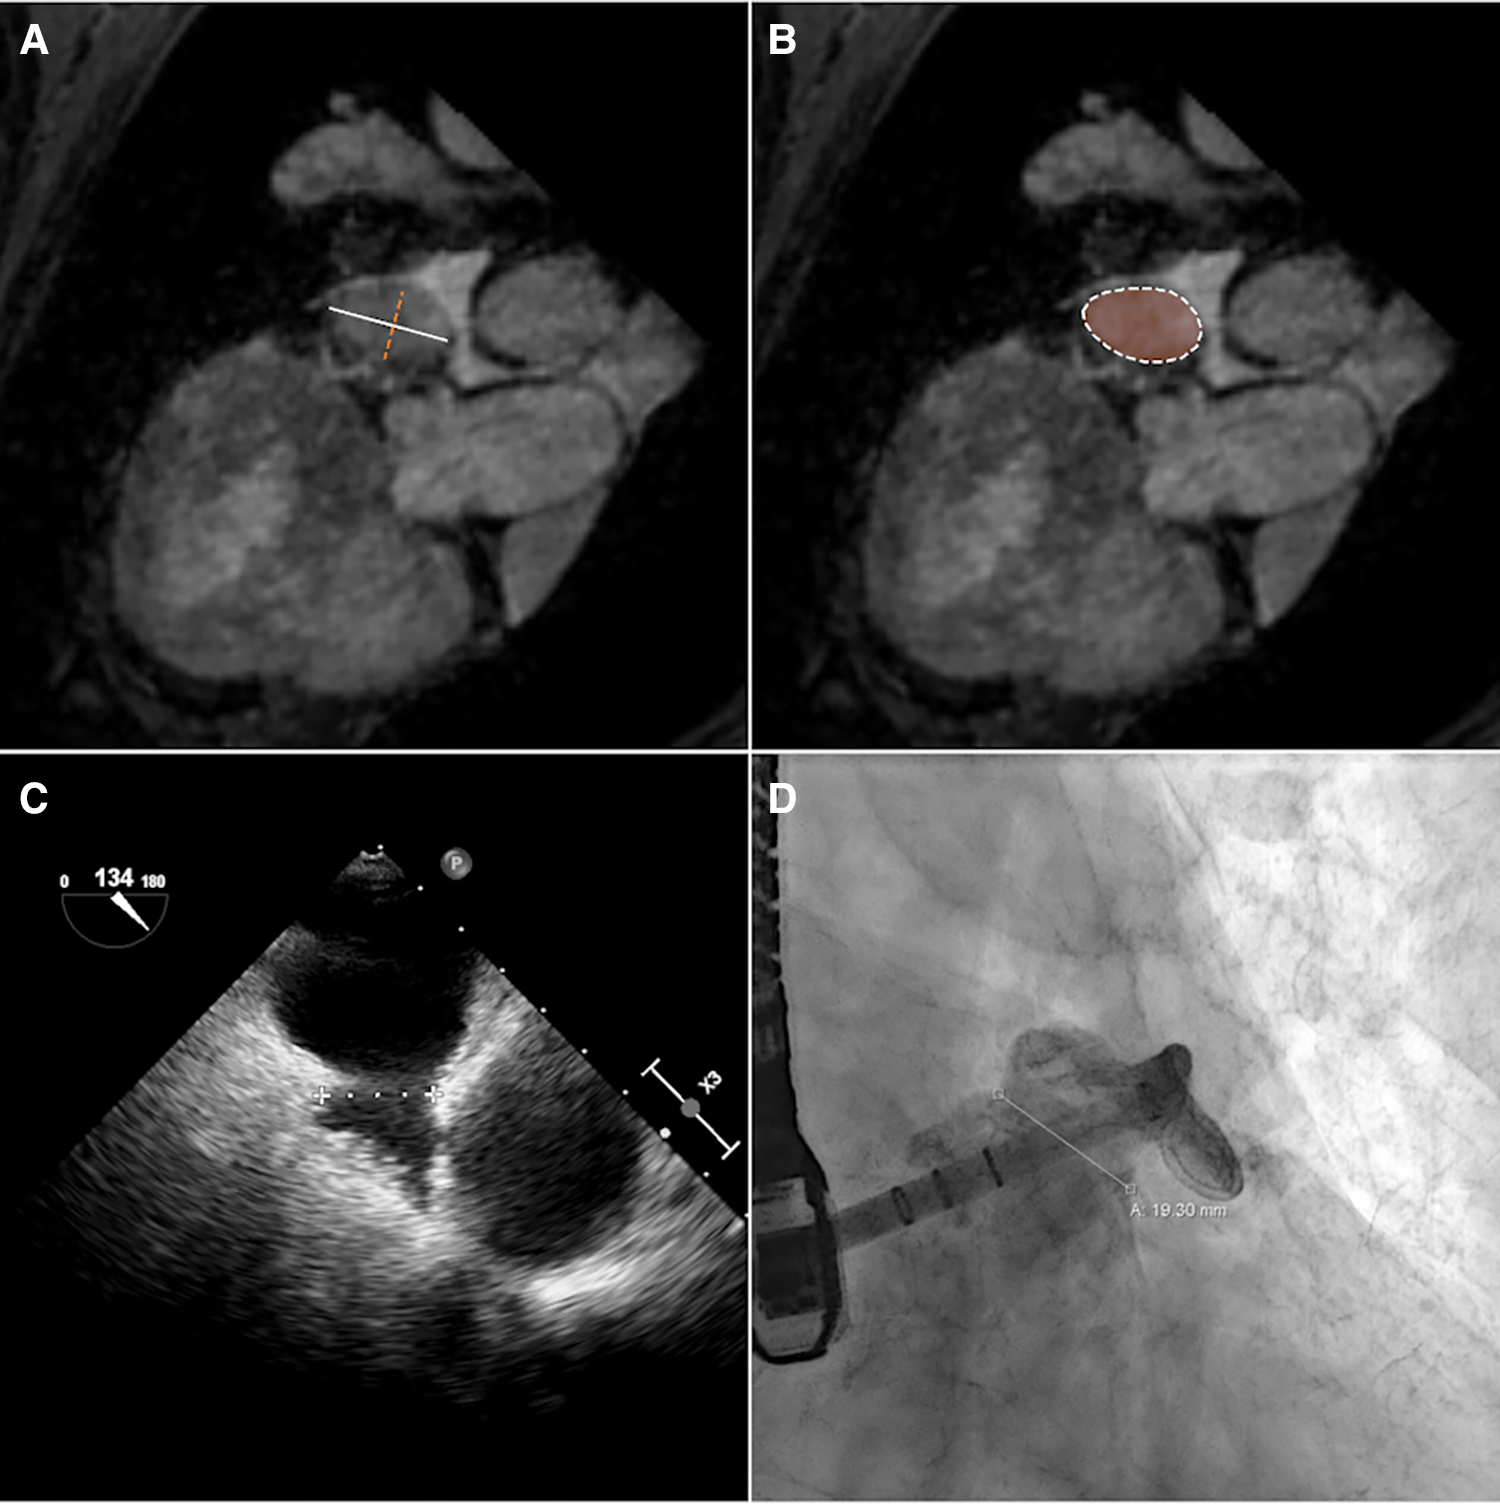

The maximum diameter (dmax), the perimeter (p) derived diameter (dperi = ), the area (a) derived diameter (darea = ), and minimum diameter (dmin) of the CMR-derived landing zone were quantified in the CMR images (Figures 2A,B). CMR-derived measurements were compared with periprocedural measurements derived from XR (dXR) and TEE (dTEE) (Figures 2C,D). The ovality of the landing zones derived from dmax and dmin was correlated with the deviations of dmax to dXR and dTEE.

Figure 2

The diameter of the landing zone measured by CMR (A,B), TEE (C), and XR (D). Based on CMR, maximum (A, white solid line) and minimum (A, orange dashed line) diameters and diameters calculated from perimeter (B, white dashed line) and area (B, orange area) measurements of the landing zone were derived.